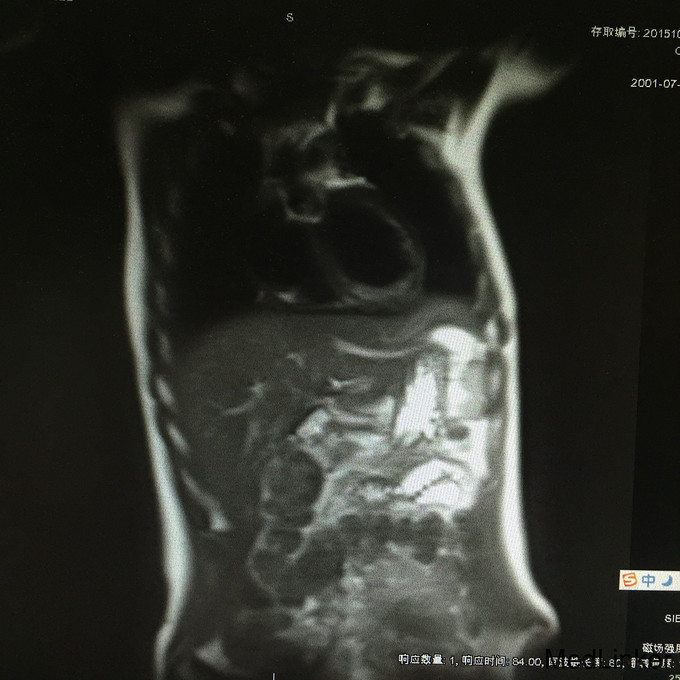

查体:生命体征平稳;双侧乳腺发育稍差。妇检:外阴呈女性生殖特征,阴蒂肥大,可见尿道开口;阴道外口可见,无性生活史,未内诊。肛查示子宫小,盆腔右侧可及包块。 辅查:2015-08-15妇科B超示:子宫小,左侧卵巢内未见明显卵泡结构;右侧附件区囊性肿块,待排畸胎瘤(43mm*30mm)。 2015-08-24查染色体示46XY,t(4;20)(q27;p13)。 2015-09-28我院查盆腔MR示双侧附件肿块,性质待定,考虑卵巢来源;阴茎发育短小,子宫小,符合双性畸形改变。

诊断:两性畸形 治疗:请我院资深超声科主任医师复查妇科B超示双侧两性母细胞瘤可能。查腹部MR:1.右侧附件区囊实性肿块,左侧附件区实性肿块,性质待定,考虑卵巢来源肿瘤。 2.阴茎发育短小,子宫稍小,符合双性畸形改变。 3.双侧肾脏及输尿管、膀胱MRI扫描未见异常。 4.上腹部MRI扫描未见异常。 请儿科教授会诊,46XY性发育障碍,意见:女性表型含Y染色体者发生性腺恶性肿瘤可能性大,建议腹腔镜性腺切除。查皮质醇8AM正常及ACTH 8AM,均正常。行腹腔镜下双侧性腺肿瘤切除术+双输卵管切除术。术中冰冻结果:良性。